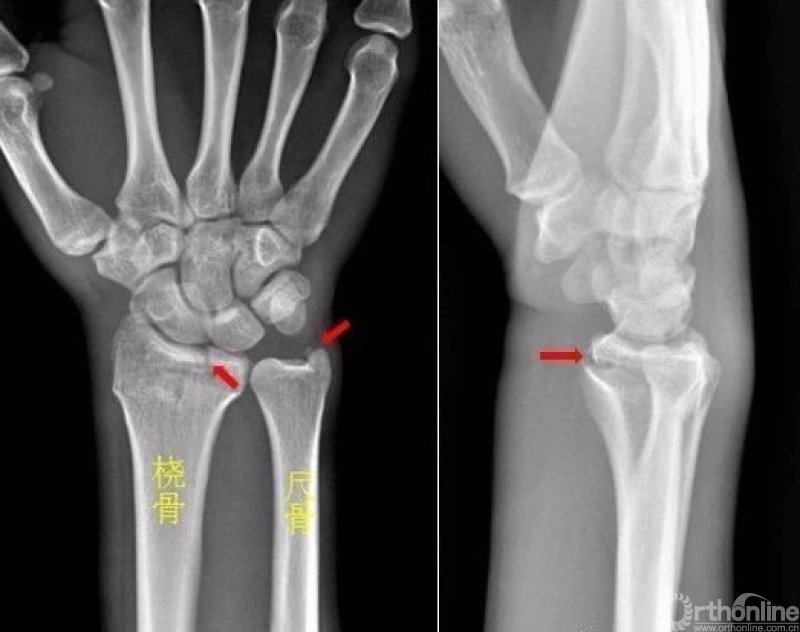

右侧桡骨远端可见不规则透亮骨折线,并累及关节面。右侧桡骨远端骨折

尺骨茎突见游离骨碎片影。左侧尺骨茎突骨折